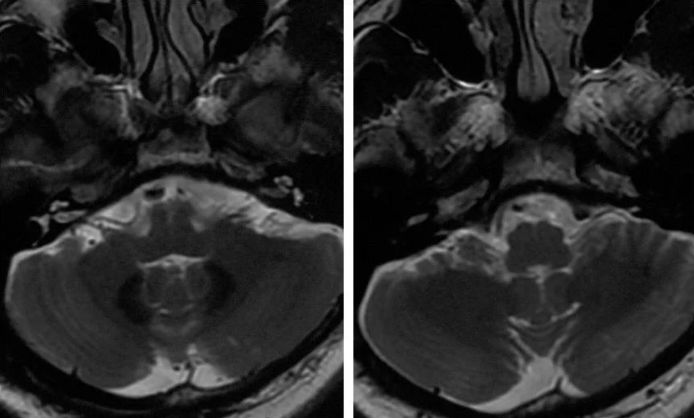

患者,男,46岁,主因“头晕3个月,眩晕伴恶心呕吐2个月”入院。患者3个月前突发头晕,伴头部昏沉感,持续时间短,程度轻,初未予重视。2个月前出现眩晕,伴恶心呕吐,就诊当地医院,行头颅MRI:左侧小脑小灶梗死,右椎动脉V4段狭窄,基底动脉远段显影欠佳,左椎动脉V4未见显影(图1,2)。

图1

图2